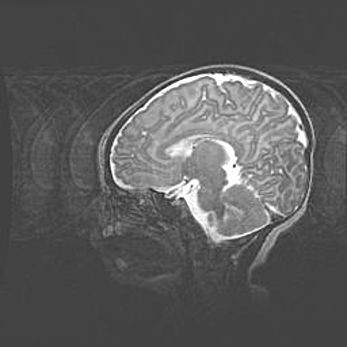

Церебральная ишемия II.

Возраст: 5 дней

Вес: 3400 г

Пол: женский

Окружность головы: 35 см

Срок гестации: 39 недель

Церебральная ишемия – это заболевание, характеризующееся недостаточностью (гипоксией) либо полным прекращением (аноксией) снабжения мозга кислородом по причине закупорки одного или нескольких сосудов. Это приводит к  что метаболическим расстройствам различной степени тяжести в тканях головного мозга, развитию коагуляционных некрозов и гибели нейронов.